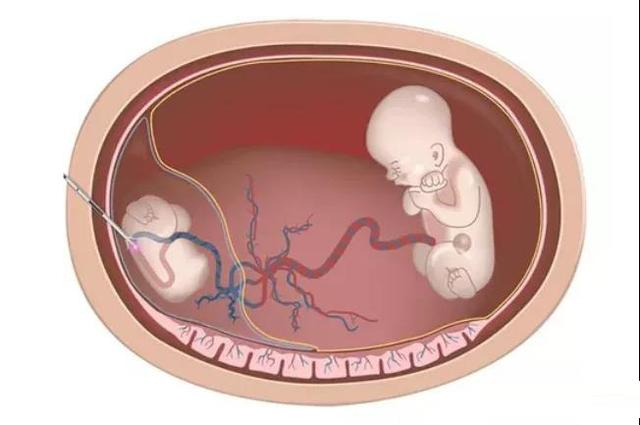

2、射频消融术减胎

如果在妊娠中期,其中一个胎儿发育不全,想要减少胎儿,射频消融术是一种选择。在超声引导下将射频消融电极植入待缩胎儿脐轮内,进行射频消融,使发育不全的胎儿坏死,达到缩胎的目的。